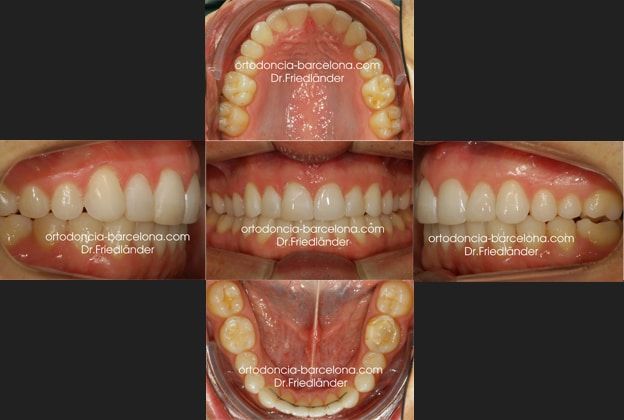

Después de 20 meses y un refinamiento se consiguió clase I en ambos lados y centrar la línea media inferior con la superior.

Podemos ver que el final del tratamiento en boca coincide perfectamente con la planificación del Clincheck final

Antes y después

Cambios en la sonrisa: